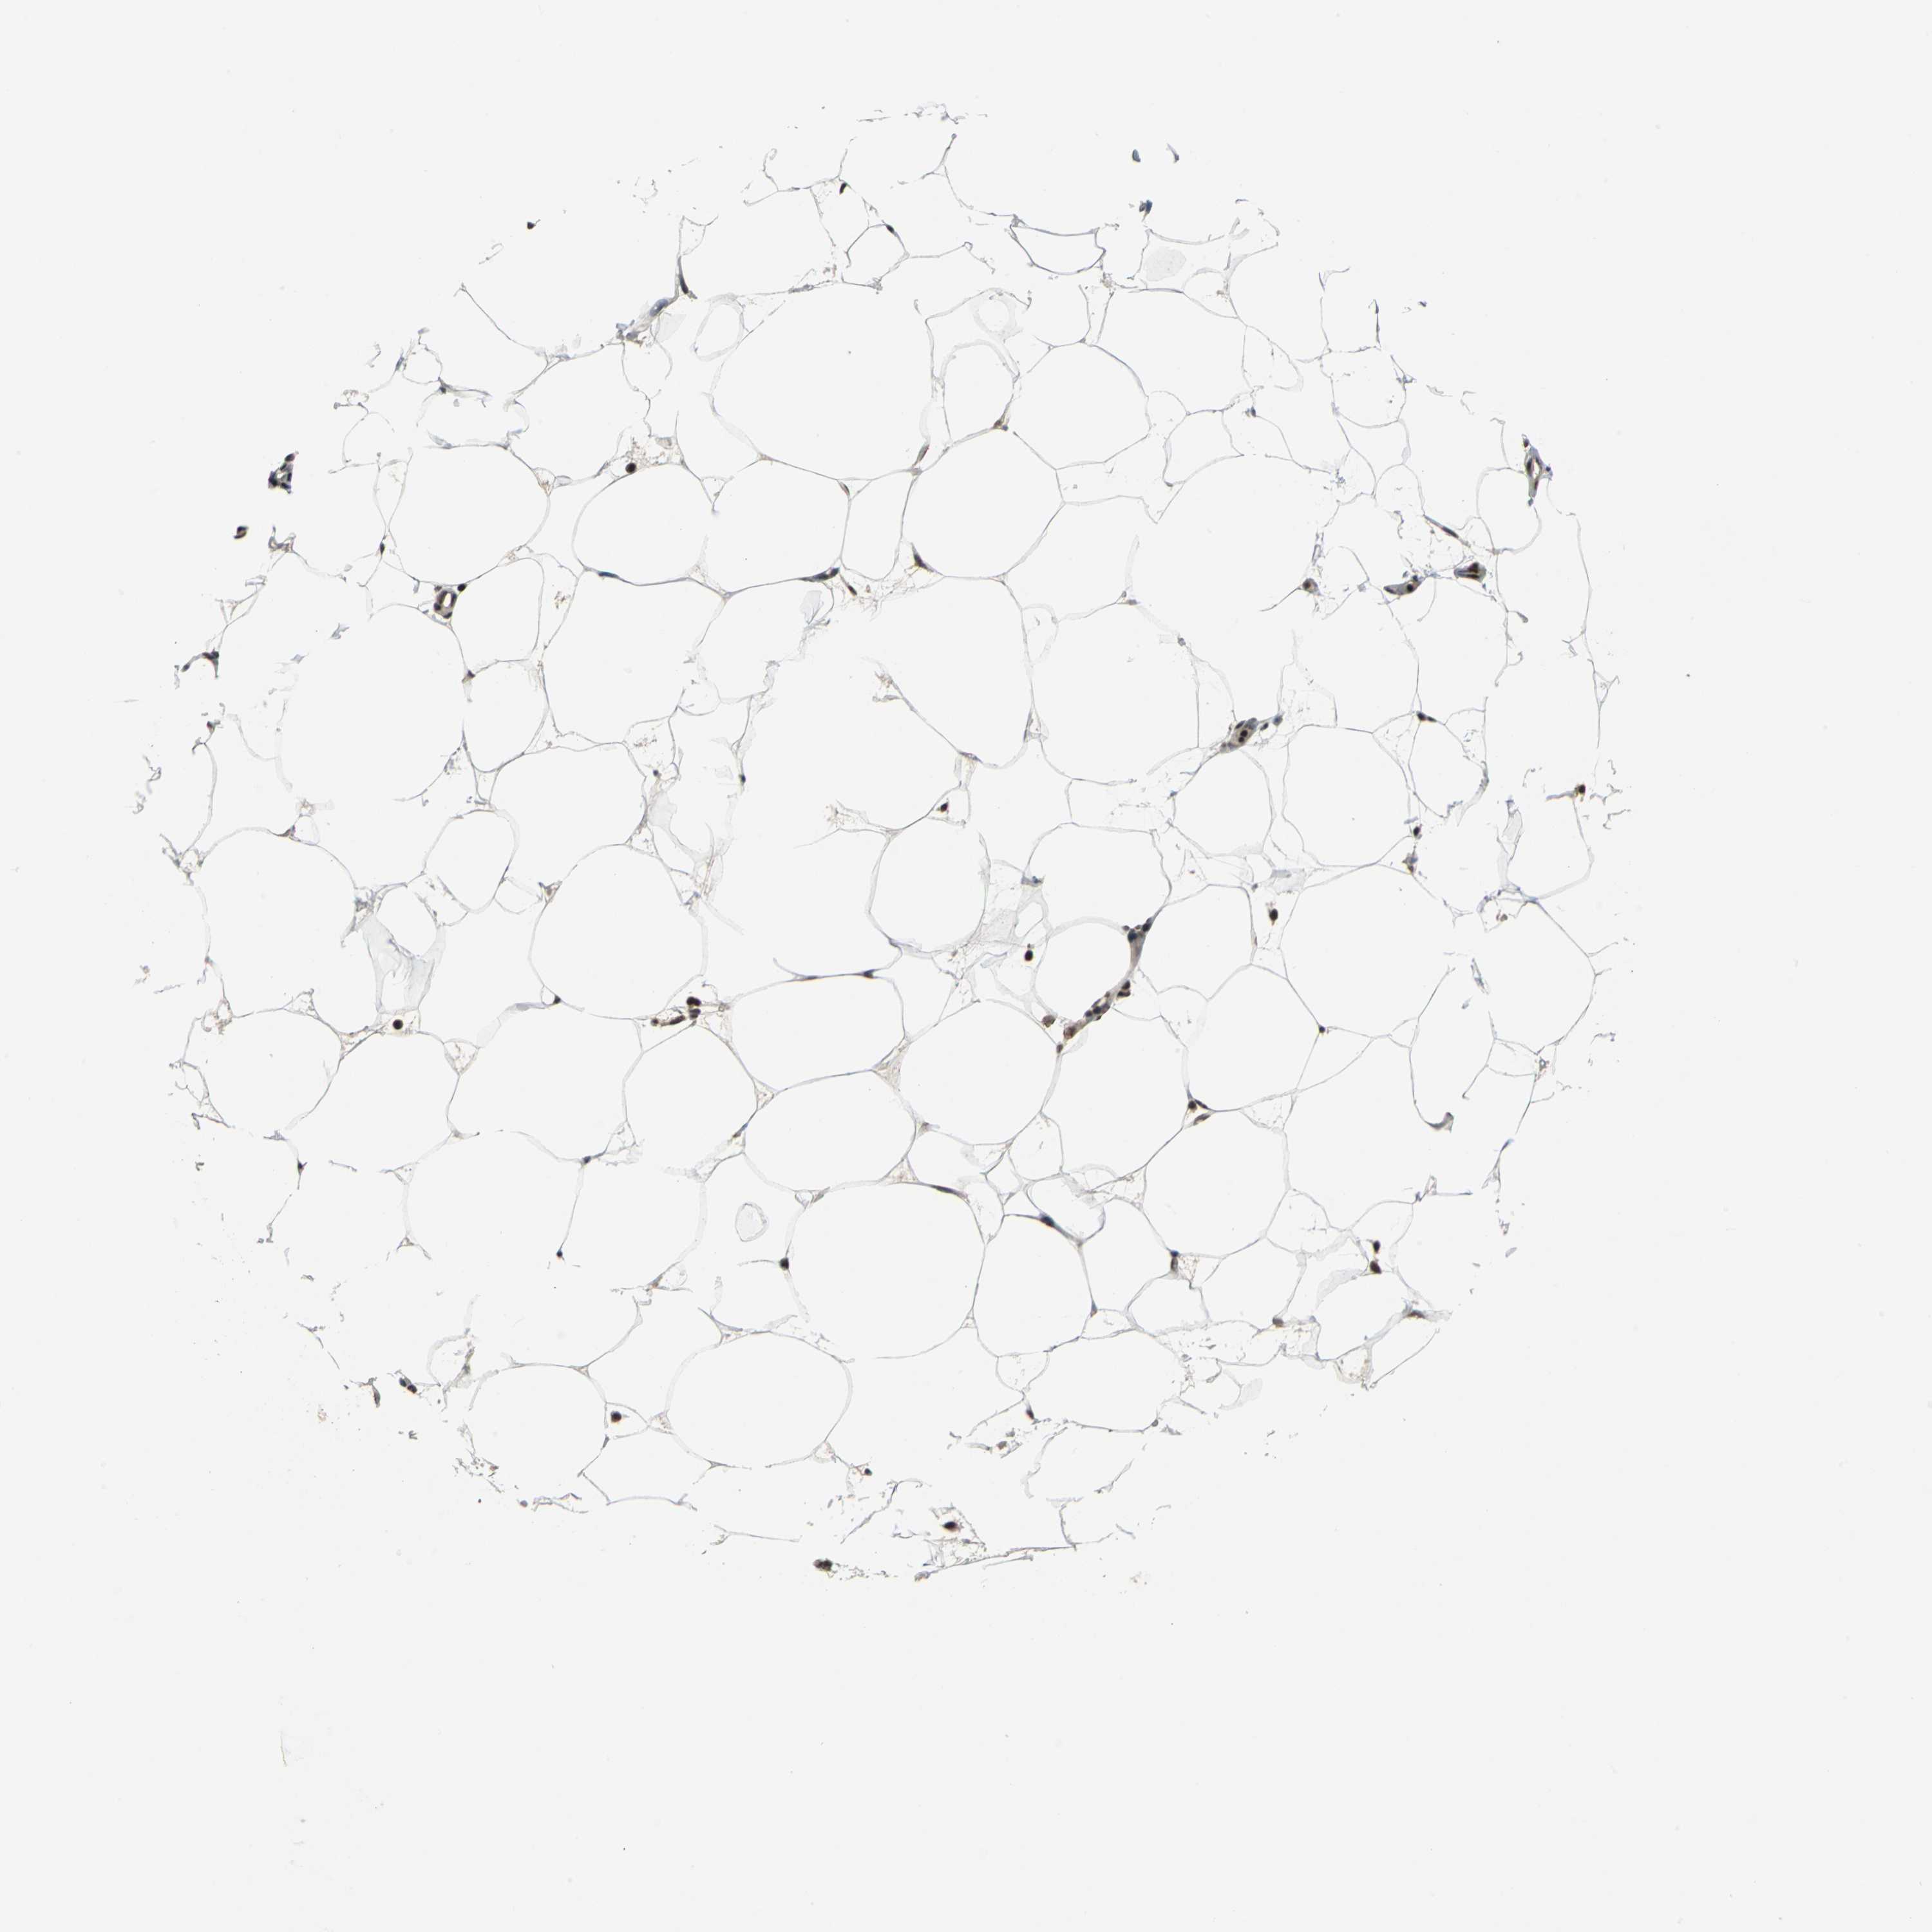

SOFT TISSUE 2 - Antibody stainingi

Antibody staining in the annotated cell types in the current human tissue is reported as not detected, low, medium, or high, based on conventional immunohistochemistry profiling in selected tissues. This score is based on the combination of the staining intensity and fraction of stained cells.

Each image is clickable and will lead to virtual microscopy that enables deeper exploration of all samples and also displays staining intensity scores, fraction scores and subcellular localization as well as patient and tissue information for each sample.

Antibody HPA006628

Fibroblasts Medium

Peripheral nerve Medium